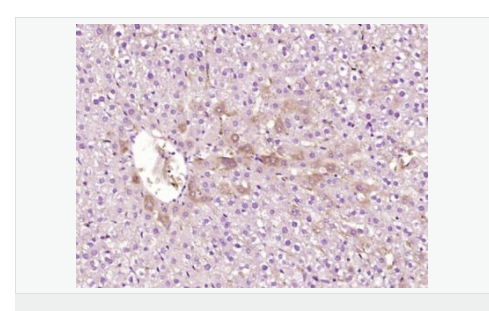

| 產(chǎn)品應用 | WB=1:500-2000 ELISA=1:5000-10000 IHC-P=1:100-500 IHC-F=1:100-500 IF=1:100-500 (石蠟切片需做抗原修復) not yet tested in other applications. optimal dilutions/concentrations should be determined by the end user. |